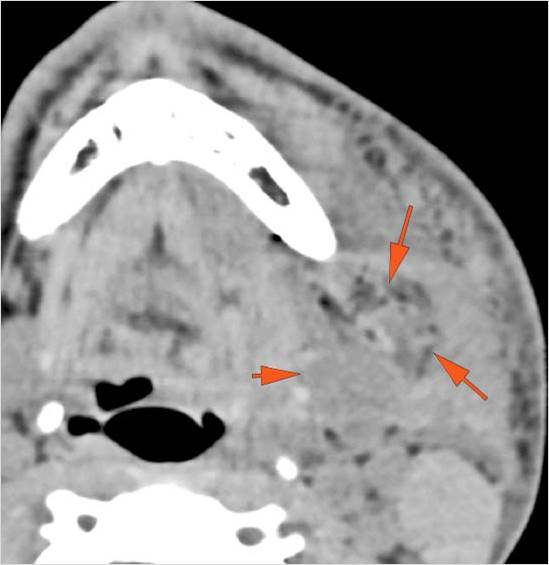

Facial and Scalp Soft Tissues and Airway

There is localized edema, hematoma or abscess within in the facial or scalp soft tissues, SMAS, infratemporal fossa, masticator space or oral cavity.

There is soft tissue swelling suggesting injury to the parotid or submandibular glands.